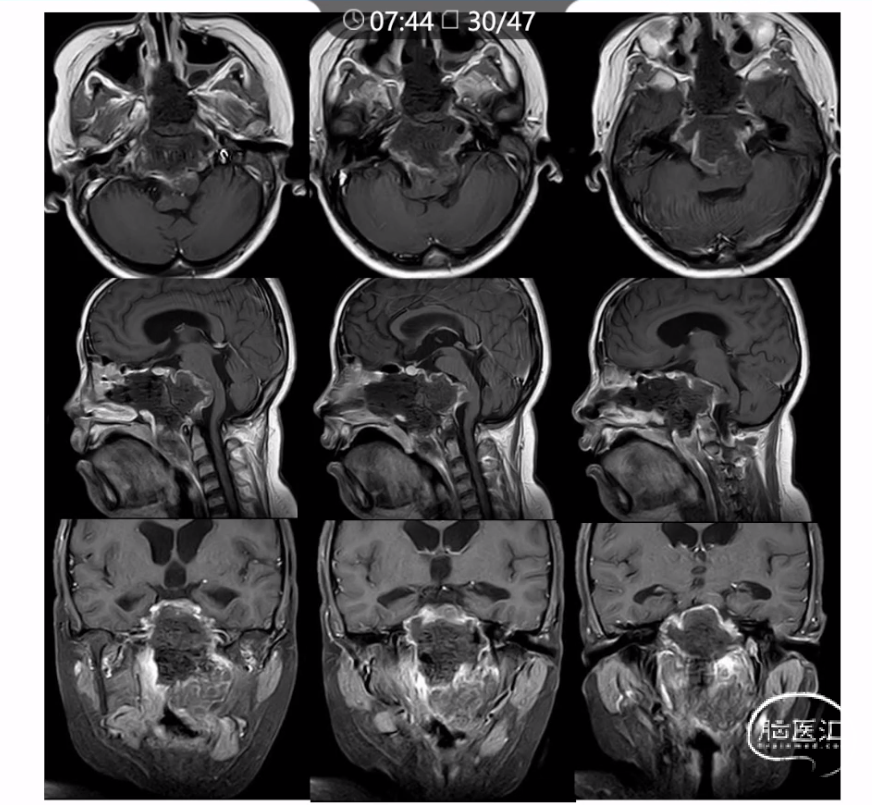

本文主要内容为:脊索瘤临床特点、治疗选择,以及多个手术病例。